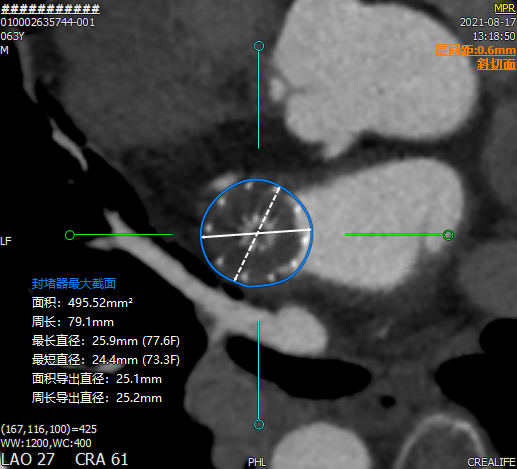

术后2个月CT三维重建,直观查看封堵器植入形态,且从二维图像来看,未见残余分流。

术后

封堵后透明三维

术后2个月未完全内皮化,未见DRT。

CT随访后提示左心耳封堵完全,遂停用达比加群,予以双联抗血小板药物进行治疗。